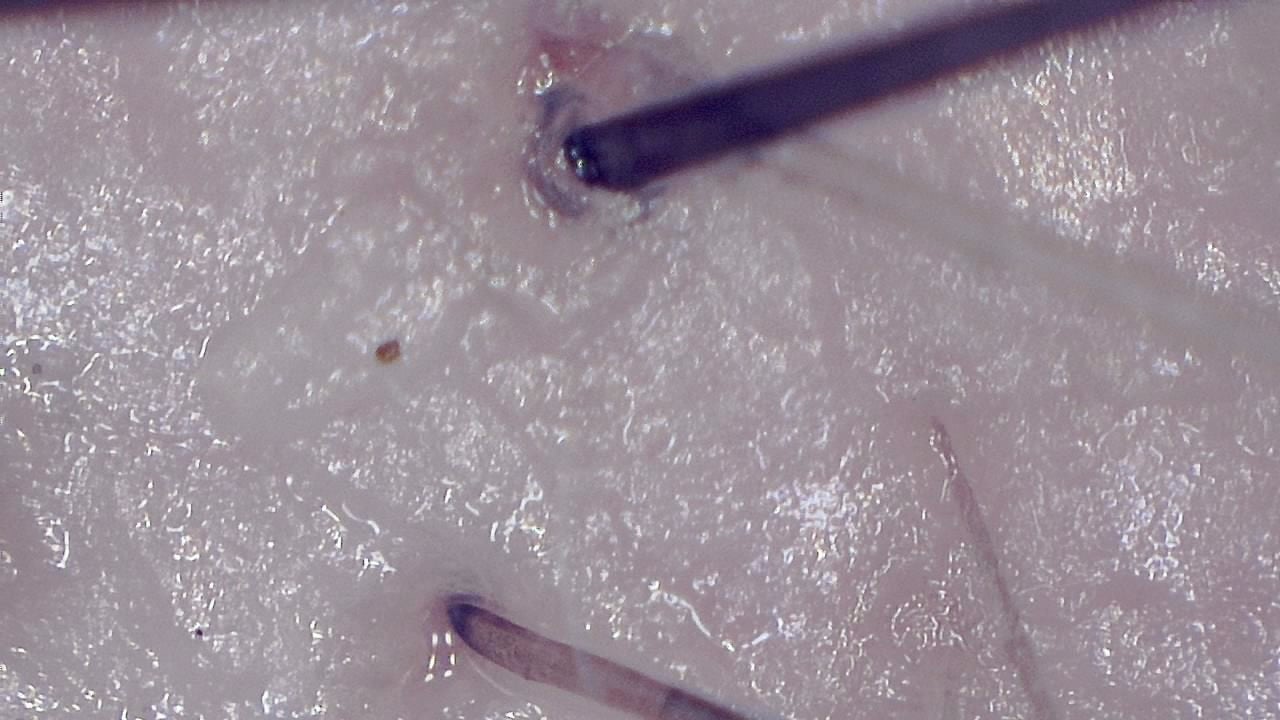

Portable magnified viewing for scalp surface, hair shafts, follicular openings, and visual documentation over time.

Trichoscopy is a non-invasive visual examination technique used by trained professionals to observe the scalp surface and hair shafts. Smart G-Scope provides a portable USB workflow for magnified viewing and image capture.

The device can support documentation of hair shaft appearance, scalp surface features, follicular openings, and visible changes over time. It is most useful when images are captured under consistent lighting and positioning.

What you can observe

- Scalp surface texture and visible follicular openings.

- Visible scaling, residues, or surface changes that need professional interpretation.

- Magnified viewing of hair shafts, scalp surface, and visible follicular openings.